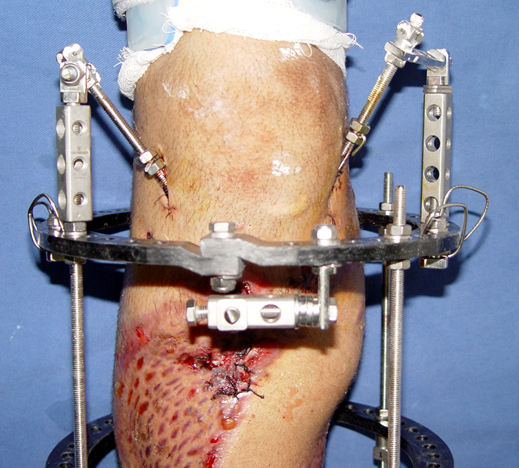

Recently, ilizarov techniques which is basis depend on distraction osteogenesis , bone segment transport or acute shortening after the resection at the site of pseudarthrosis combined with lengthening at another level of bone have been used. These treatment techniques may include some advantage for problems of infection, leg-length discrepancy, soft-tissue loss, and joint contracture.

Case 2